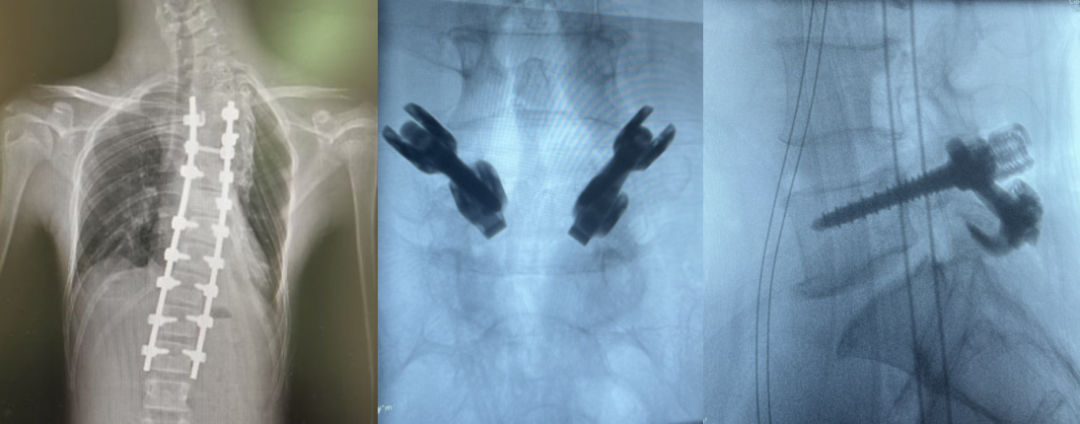

手術治療

比較嚴重的脊柱側彎需要進行手術,手術也分為多種方法,根據進行程度來進行選擇。

手術方式可以分為側前方手術和后路手術進行固定矯形植骨融合。

LEO胸腰后路釘棒系統

應對絕大部分脊柱側彎手術需求,功能強大配件齊全。